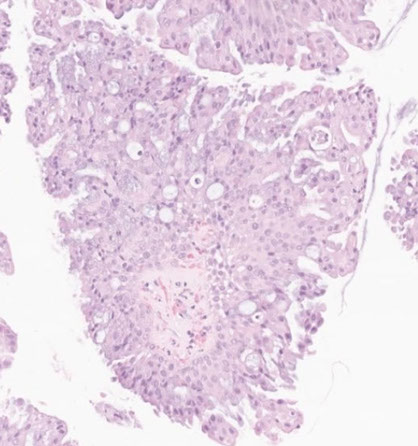

Micropapillary adenoca (arrows; surrounded by lepidic growth) [5]

Micropapillary adenocarcinoma

Even if papillae surrounded by lepidic pattern, call it micropapillary (see image)

Even if papillae surrounded by lepidic pattern, call it micropapillary